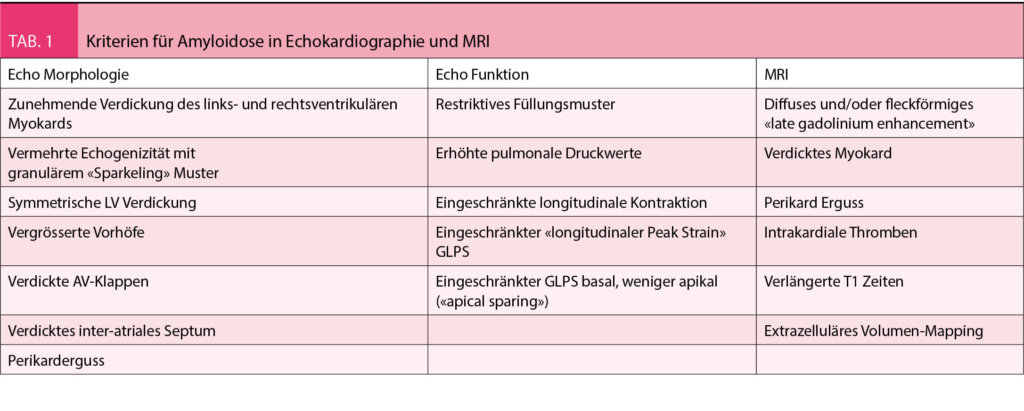

An eine kardiale Amyloidose sollte immer dann gedacht werden, wenn sich ein Patient mit Symptomen einer Herzinsuffizienz präsentiert und einen Echokardiographie- oder MRI-Befund aufweist der typisch für eine Amyloidose ist (Abb. 1 und Tab. 1) (1).

Bei Verdacht auf eine kardiale Amyloidose (Herzinsuffizienz-Beschwerden, typisches Echo oder MRI) sollten zuerst ausführliche Laboruntersuchungen inkl. kardiale Biomarker NT-pro BNP und Troponin (zur Abschätzung der Prognose) und eine Protein-Elektrophorese mit Immunfixation im Serum und Urin sowie Bestimmung der freien Leichtketten im Serum veranlasst werden. Letzteres ist entscheidend für die Unterscheidung zwischen AL und ATTR Amyloidose. Ein EKG sollte geschrieben werden, um die Frage nach Vorhofflimmern und Blockierungen zu beantworten. Die typischerweise beschriebene «low-voltage» findet sich eher bei der AL-Amyloidose, bei der ATTR ist dies jedoch nicht so häufig (ca. 22%), typischer ist dort ein Pseudoinfarktmuster (63%). Bei unauffälliger Immunfixation ist eine AL-Amyloidose praktisch ausgeschlossen (Abb. 2). In diesem Fall sollte eine Technetium Szintigraphie durchgeführt werden. Fällt diese positiv aus, gilt die Diagnose einer ATTR-Amyloidose als gesichert (4), jedoch kann nicht zwischen wtATTR und vATTR unterschieden werden, weswegen eine genetische Testung sinnvoll ist. Diese kann nach Einholen einer Kostengutsprache durch die Krankenkasse durchgeführt werden kann. An eine hereditäre Form sollte insbesondere dann gedacht werden, wenn neurologische Symptome wie Polyneuropathie vorhanden sind. Bei negativer Szintigraphie und persistierend hohem Verdacht auf eine kardiale Amyloidose, sollte eine Endmyokardbiopsie durchgeführt werden (5). Bei pathologischer Immunfixation und Verdacht auf eine kardiale Amyloidose ist die Situation etwas komplizierter, da die Diagnose mittels Biopsie und Nachweis von Amyloid gestellt werden muss. Normalerweise erfolgt bei pathologischer Immunfixation eine hämatologische Abklärung, gelegentlich gelingt der Nachweis von Amyloid schon in der Knochenmarksbiopsie (ca. 50%), ansonsten muss Amyloid an anderen Stellen (typischerweise Bauchfett, Speicheldrüsen, Endomyokard) gesucht und immunhistochemisch bestätigt werden, was gelegentlich herausfordernd sein kann (Abb. 2). Ein wichtiges Problem stellt die hohe Koinzidenz eines MGUS mit der wtATTR Amyloidose im fortgeschrittenen Alter dar.